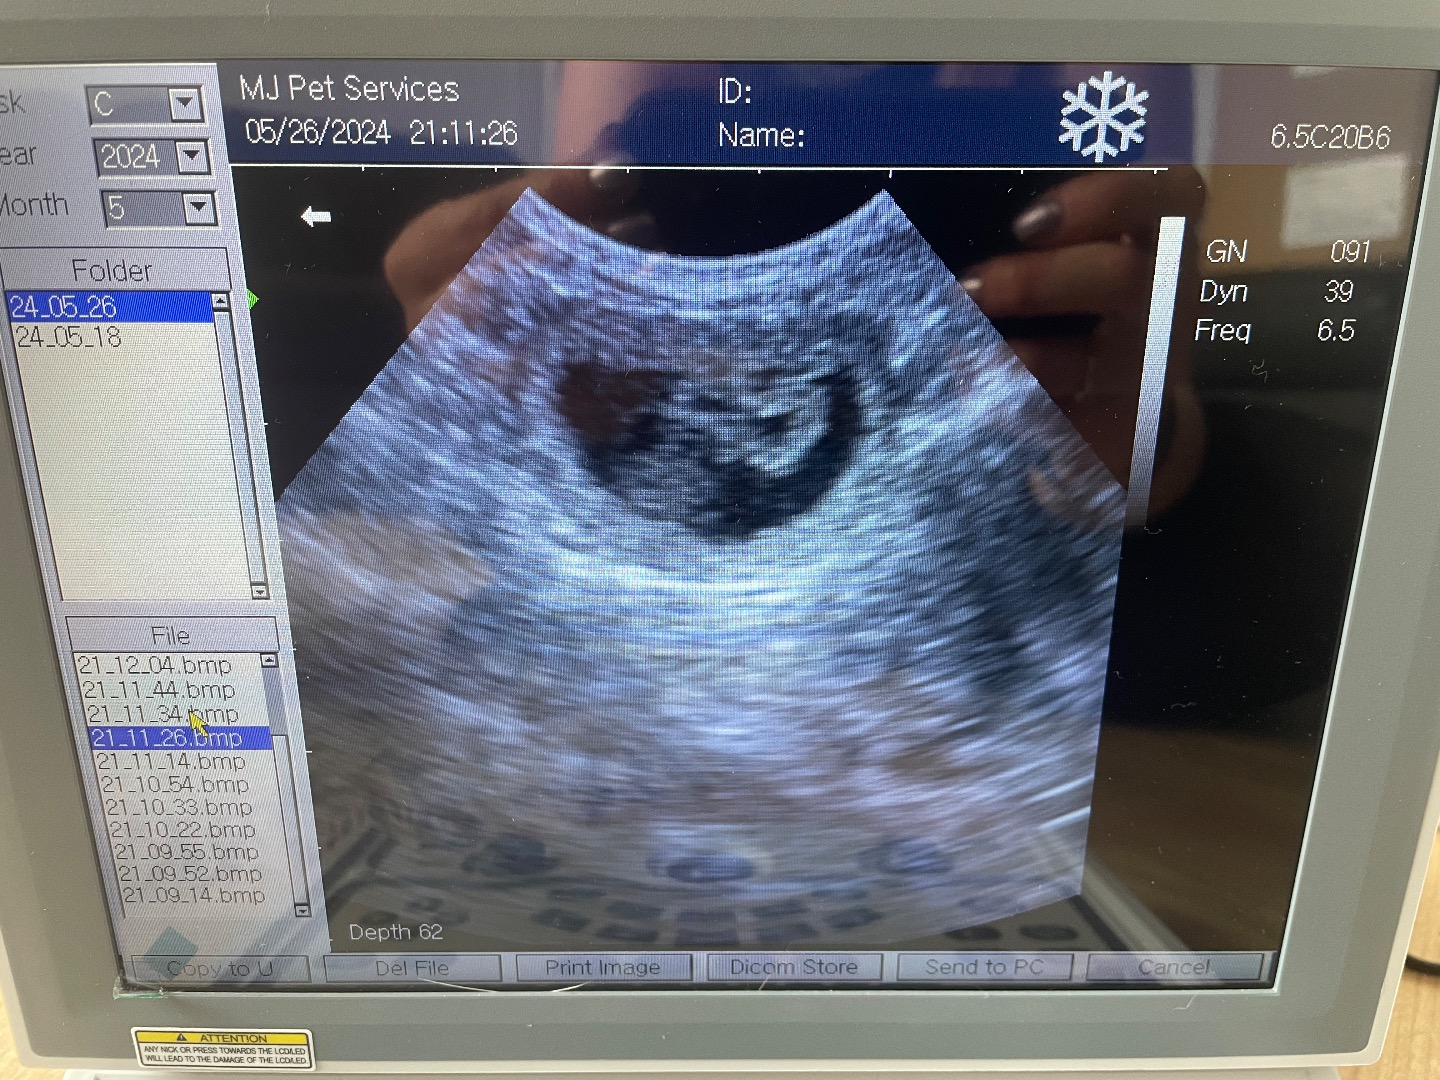

Toy Poodle scan (peaches)

Urgent vet referral scan, no pups, lots of fluid, dog ended up have emergency operation